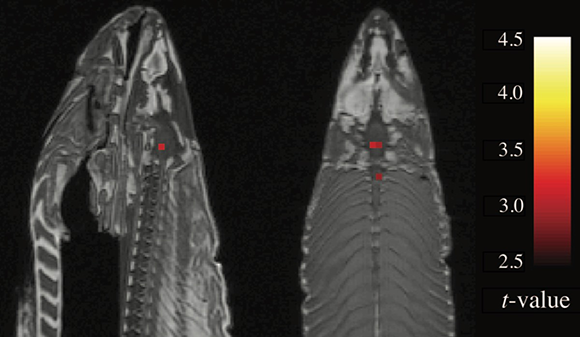

לבנט היה רעיון – הוא הציע לשלוף את הנתונים של הסלמון הקפוא, שהכילו כ-65 אלף ווקסלים, ולחפש ווקסלים פעילים. אם ימצאו ווקסלים כאלה בדג מת, זה ידגים היטב את קיומה של טעות מסוג 1 בבדיקה ולחשיבות של מציאת תיקון להשוואות מרובות. מה שציפה למצוא היה פיזור אקראי של ווקסלים בודדים, אך להפתעתו ראה בנט שלושה צברים ברורים של ווקסלים פעילים – דפוס פעילות שממש לא אמור להימצא במוחו הדומם של הסלמון הקפוא.

בנט מיהר להציג את ממצאיו בכנס בינלאומי חשוב שנערך באותה שנה, לאחר ששכנע את מארגניו שלא מדובר במתיחה. המחקר עורר תגובות רבות – היו כאלה שראו בו מתיחה טיפשית, ואחרים טענו שבוודאי נפלה טעות בתהליך ניתוח הנתונים. בנט הבין שלמרות החשש ממה שמחקר טיפשי על דג מת יעשה לשמו הטוב כמדען בתחילת דרכו, יש בידו ממצאים שצריך לפרסם. בשנת 2009 פרסמו בנט ועמיתיו את ממצאי סריקת ה-fMRI של הסלמון. המאמר הצית דיונים סוערים בקהילת החוקרים העולמית, ואף זיכה את כותביו בפרס איג נובל בשנת 2012.

בנט ראה להפתעתו שלושה צברים ברורים של ווקסלים פעילים – דפוס פעילות שלא אמור להימצא במוחו של הסלמון הקפוא. סריקת ה-MRI של הדג המת | Bennett, C. et al. JSUR (2010), CC BY 3.0